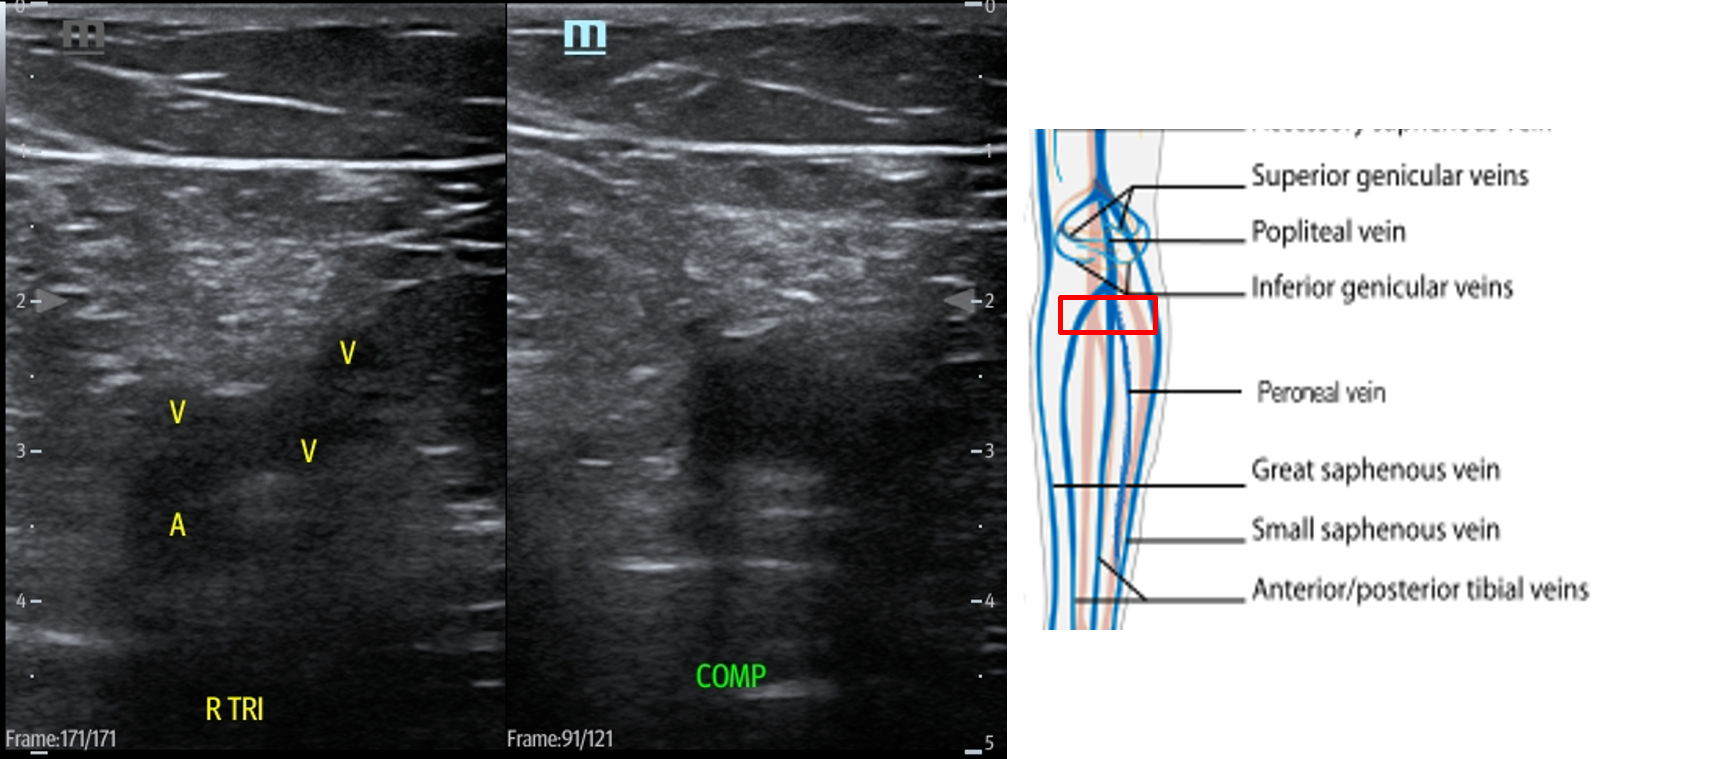

- In the popliteal region, you should see the popliteal vein (PV) superficial to the popliteal artery (PA). (Fig. 14) If you see more than one artery and one vein, slide the transducer proximally until you see the PV and PA. When you have this view, compress as before.

- Figure 14. Compression of the popliteal vein in the popliteal fossa with transducer orientation indicated (red rectangle).

- Slide the transducer distally until you see the PV trifurcate into the PTV, ATV and peroneal vein. (Fig. 15) Compress each of these veins. This constitutes completion of evaluation of “region 2.”

- Figure 15. Compression of the PTV, ATV and peroneal vein in the distal portion of the popliteal fossa just before they converge into the popliteal vein with transducer orientation indicated (red rectangle).